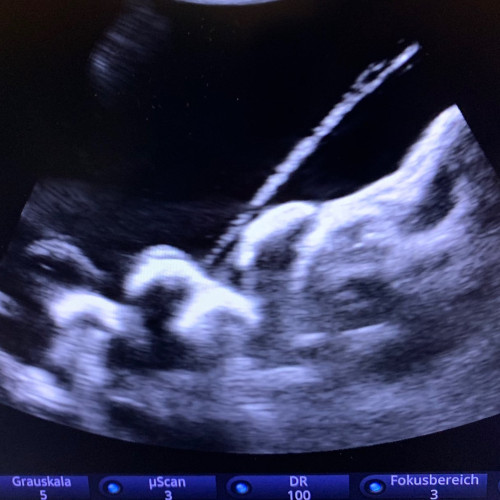

Ultraschall-gezielte Infiltrationsbehandlung – Es handelt sich dabei um eine Ultraschall-gezielte Infiltration ohne Strahlenbelastung. Dadurch können Schmerzen schnell und effektiv behandelt werden. Diese Infiltration kann bei mir in der Ordination durchgeführt werden.

- Ultraschallgezielte Infiltration der Facettengelenke, Nervenwurzeln, ISG und epidurale Flutungen von caudal